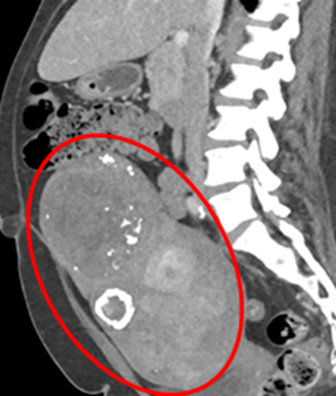

Additional Images

Contrast-enhanced CT images of the abdomen and pelvis are provided.

Quiz 2

1. What is the principal finding on the CT scan?

(1) Hepatic laceration

(2) Dilated loop of small bowel in the right lower quadrant

(3) Large calcified fibroid uterus

(4) Inguinal hernia containing small bowel loops

Explanation:

The contrast-enhanced abdominopelvic CT shows a large, heavily calcified uterine mass located in the pelvic cavity, consistent with a degenerating (calcified) uterine leiomyoma.

• Hepatic laceration (1) would appear as a linear or irregular hypodense area in the liver parenchyma, which is not seen here.

• Dilated bowel loop (2) and inguinal hernia (4) typically present with air-fluid levels or herniated bowel segments, which were not identified.

• The mass's location, morphology, and dense peripheral calcification are pathognomonic for a fibroid (leiomyoma) undergoing calcific degeneration.

Uterine fibroids are common in women over 50 and may undergo various forms of degeneration, with calcification being a typical late finding, especially postmenopausally.

Contrast-enhanced abdominal and pelvic CT demonstrates marked uterine enlargement due to multiple calcified fibroids, with the uterus extending cranially into the right lower abdomen.

• CT: May show soft tissue density in the pelvis, distorting the smooth contour of the uterus. Peripheral or central calcifications may also be noted.